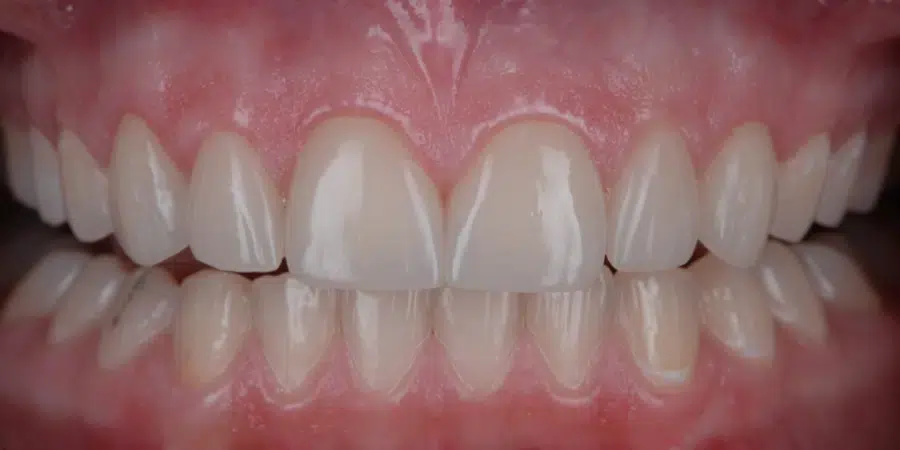

După

Caz de estetică dentară – Fațete ceramică presată E-Max

Provocarea acestui caz a fost în prepararea minim invazivă a dinților centrali rotați și a obține o formă și o culoare cât mai naturală, pacienta dorind un caz de estetică dentară ce să nu fie observabil.

Pacienta a beneficiat de corecție gingivala cu laser pentru uniformizarea asimetriilor gingivale, tratamente endodontice de canal sub microscop, obturațiile vechi (plombe) schimbate cu materiale de compozit cu particule nanoceramice, și fațete dentare din ceramică presată E-Max.

Termen de finalizare 2 săptămâni de la amprentarea finală.